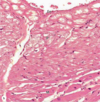

Smooth Muscle

IC - Inner circular layer

OL - Outer longitudinal layer

Arrows - Muscle nuclei

Smooth Muscle

XS - Cross section

LS - Longitudinal section

PP - Perimysium

Smooth Muscle